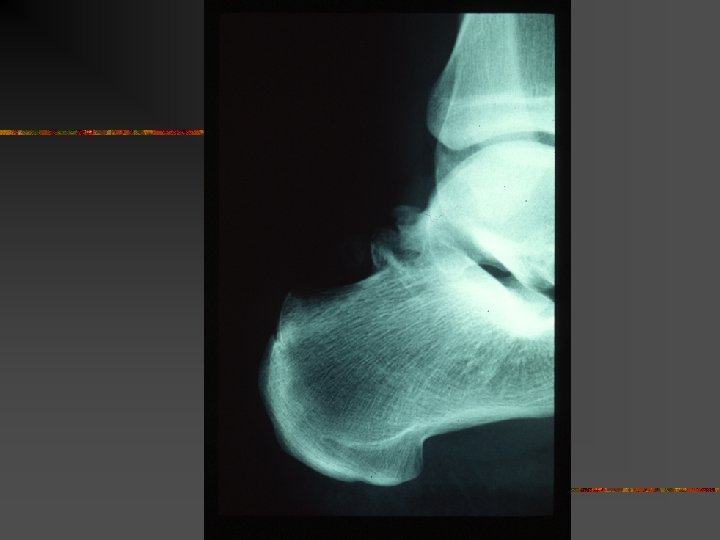

Le SCP traumatique : Mécanismes Trauma en flexion plantaire forcée n Très fréquent… n Origine : Shoot contré, tacles, irrégularité du sol, … Lésions : - contusion « postérieure » chondrales, caps. -ligamentaire - # processus post. lat. du talus (# de SHEPHERD) - # malléole tibiale postérieure - # os trigone ou de la synchondrose n Difficultés : - DD # ou os trigone… - Arguments : - # : trait net et non corticalisé - scintigraphie n

Fracture du processus postéro-latéral

# malléole postérieure

# de l’os trigone (Collection D. Richarme - Cochin)